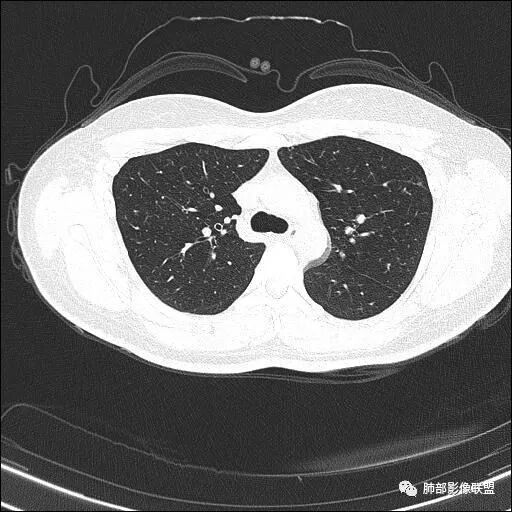

【每日晨读】双肺上叶多发薄壁空洞

双肺上叶尖段分布为主多发囊腔伴斑点,斑片影,囊腔壁不规则,部分内见分隔。考虑结核可能

两肺多发囊或空洞(部分腔内不干净可见间隔影)+多发结节 (右侧胸膜下的结节显著)+左肺尖斑片影。年轻女性,体检发现。考虑结核?鉴别PLCH(奇异囊加结节,吸烟男性多见),转移瘤(要有原发肿瘤病史)

中年女性,体检发现, 双肺上叶多发囊腔伴斑点,斑片影,囊腔壁不规则,部分内见分隔,部分可见树芽征。考虑感染性病变,结核,NTM可能。

2.双肺多发薄壁空洞影、条索影及结节影,边界较清楚,密度偏高不柔和,散乱,但有成簇倾向或堆积感,胸膜下分布为主,双肺上叶分布为主。

3.空洞相当不规则,缺乏张力,未见血管穿行,未见壁结节,未见液平。